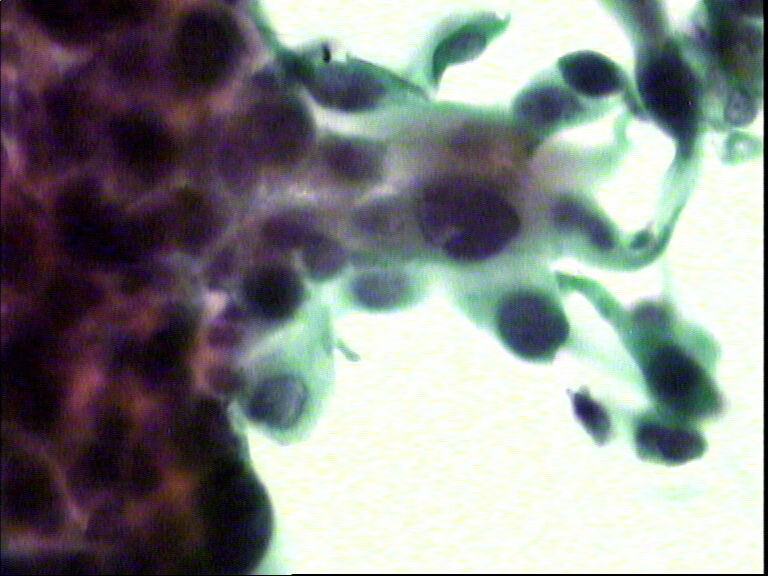

宫颈液基,老年妇女,78岁,临床:宫颈肥大

• 宫颈液基,老年妇女,78岁,临床:宫颈肥大图1

图1

HSIL,建议活检。

HSIL,疑SCC。

HSIL,不除外SCC建议活检。

宫颈高级别上皮内病变,不除外鳞状细胞癌(建议活检)。